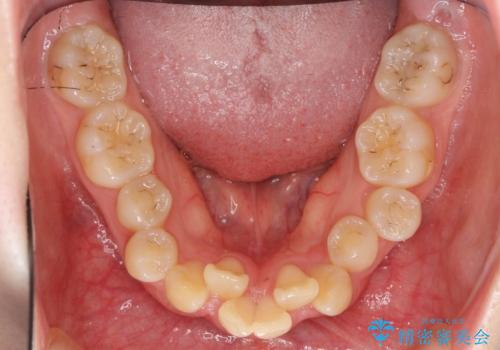

20代女性 前から5番目の歯を抜歯

- 前歯のがたつき、前突を主訴に来院。

通常前から4番目の歯を抜歯するのですが、左上5番の形が矮小であったため、そちらを抜歯しました。(患者様の希望にそっています。)

前から5番目の歯を抜くと、長くて1年ほど矯正期間が延長しますが、形に異常がない左上4番を抜かずに保存しています。